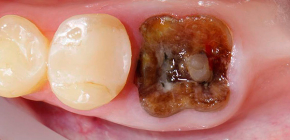

Quando la corona del dente è gravemente danneggiata (ad esempio, dalla carie o a causa di un trauma), spesso sorge la domanda di rimuovere le radici del dente. Può anche accadere che una cisti o un granuloma si formino nella parte superiore della radice del dente a causa del processo infiammatorio - in tali situazioni è talvolta possibile salvare il dente dalla rimozione mediante resezione dell'apice della radice, o anche l'intera radice malata deve essere amputata. Parleremo ulteriormente di ciò che è utile sapere sulla rimozione della radice del dente: vedremo quando, in generale, è richiesta la rimozione della radice, cosa puoi aspettarti nell'ufficio di un dentista-chirurgo e quali problemi a volte sorgono durante la procedura ...

carie